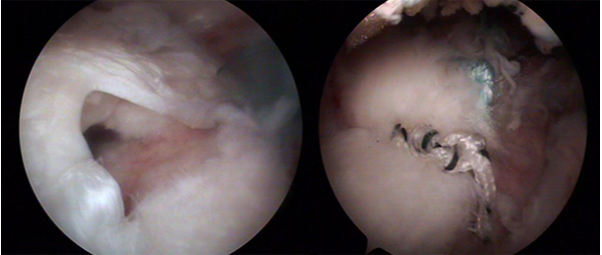

어깨 힘줄에 석회질이 생성되면서 염증이 발생하고 그것이 돌처럼 굳어지면서 심한 통증을 일으키는 질환입니다.

석회성 건염의 원인은 정확히 밝혀지진 않았으나 칼슘의 배출 과정에 문제가 있어서 어깨 인대 부위에 석회가 침착하는 것으로 알려져 있습니다. 어깨 힘줄에 혈류가 감소해 산소 분압이 떨어지면서 힘줄 세포가 연골 세포로 변해 석회질이 침착된다는 가설도 있습니다. 침착된 석회질은 하나 혹은 여러 개가 한 번에 생기기도 하고, 1mm~3cm 정도 다양한 크기로 침착됩니다. 주로 힘줄 세포가 괴사된 부위에 석회가 차서 생기고 어깨의 과도한 사용도 원이이 될 수 있습니다.